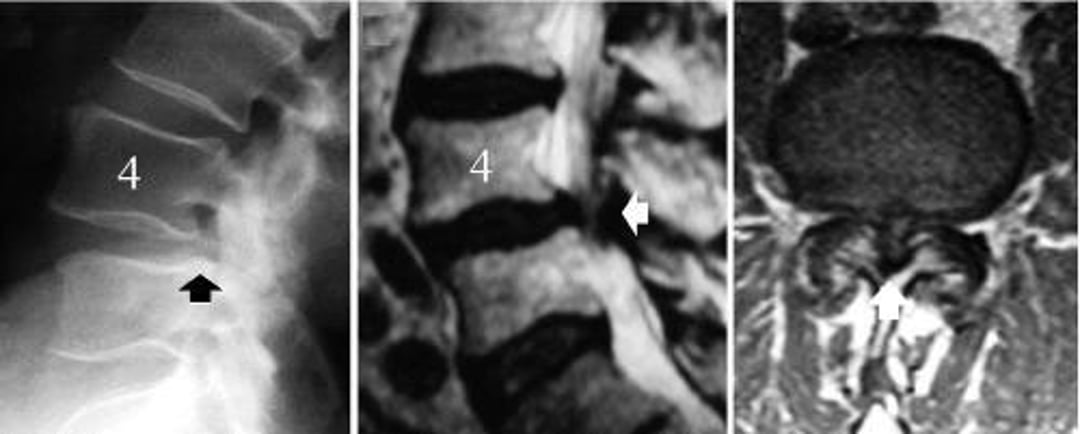

Estenosis de las vértebras lumbares causada por espondilolistesis degenerativa de L4-L5

La imagen de la izquierda es una radiografía lateral de la columna lumbar que muestra el deslizamiento de la vértebra L4 (flecha negra: el borde posterior del cuerpo vertebral L5 no se alinea con el de L4). La imagen en el medio es una RM mediosagital que muestra la compresión de las estructuras neurales (flecha blanca). La imagen de la derecha es una RM que muestra una estenosis vertebral grave a nivel de la espondilolistesis degenerativa, L4-5 (flecha blanca).